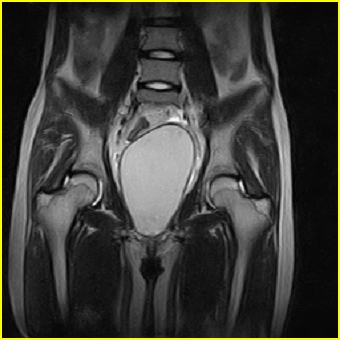

女、15岁、下腹疼痛2天,排尿困难1天。查体:处女膜闭锁,距处女膜约4至5cm处扪及一约5cm直径的圆形包块,张力较高,触痛明显、欠活动。b超提示子宫增大伴宫内增强回声团。

更正影像意见:阴道积血。

处女膜闭锁,阴道积血

处女膜闭锁,阴道积血,子宫积血.

处女膜闭锁,伴子宫及阴道积血.